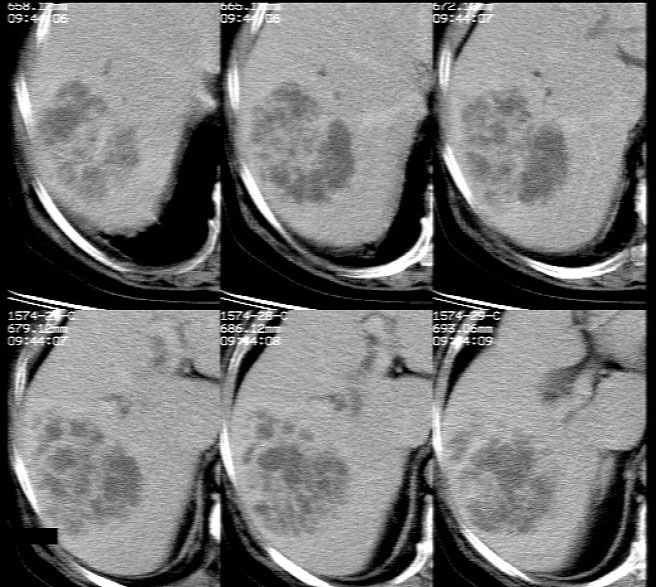

平扫示: 肝右后叶见团状低密度灶,边界欠清,密度略不均匀,ct值28-32hu,肝内胆管无扩张。

ct增强扫描示: 动脉期肝右后叶团状低密度边缘明显不均性强化,内呈不规则峰窝状低密度(无强化区),不规则分隔亦见明显强化;三期扫描像均见,病灶有明显占位征,周围血管、胆管推挤外移,病灶与正常肝组织分界不清,延迟期病灶周围见雾状略低密度(较肝左叶)。

肝右后叶团状低密度占位性病变,结合临床提示: 1、肝脓肿? 2、不排除肝ca可能。建议afp检查。

平扫示肝右后叶见团状低密度灶,边界欠清,密度略不均匀,ct值28-32hu,肝内胆管无扩张。ct增强扫描动脉期肝右后叶团状低密度边缘明显不均性强化,内见多发斑片状无强化液化区,呈不规则峰窝状。

考虑肝脓肿早期(蜂窝组织炎阶段)。

鉴别:肝血管瘤,早期周边强化明显,逐渐向中心充填。原发性肝癌,强化一般呈快进快出,多有乙肝肝硬化病史。